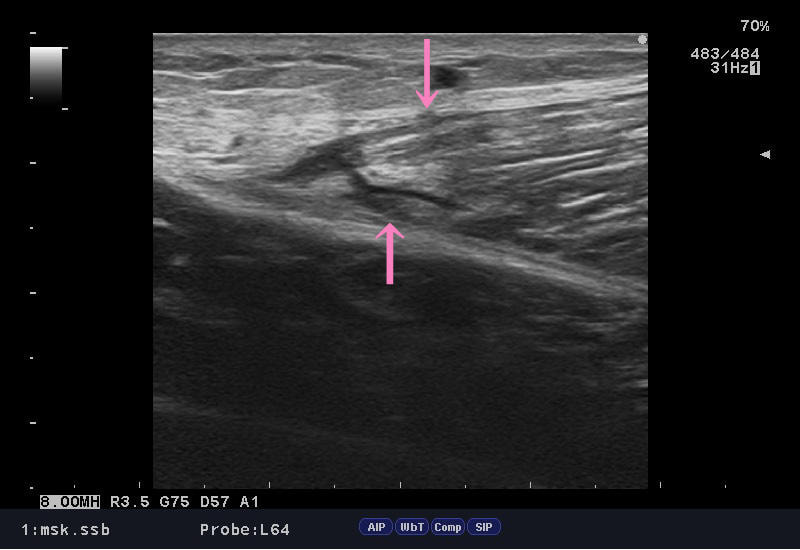

またまた「ふくらはぎの肉離れ」急増中でございます。

ランニングしていてパチン・・・プチン・・・